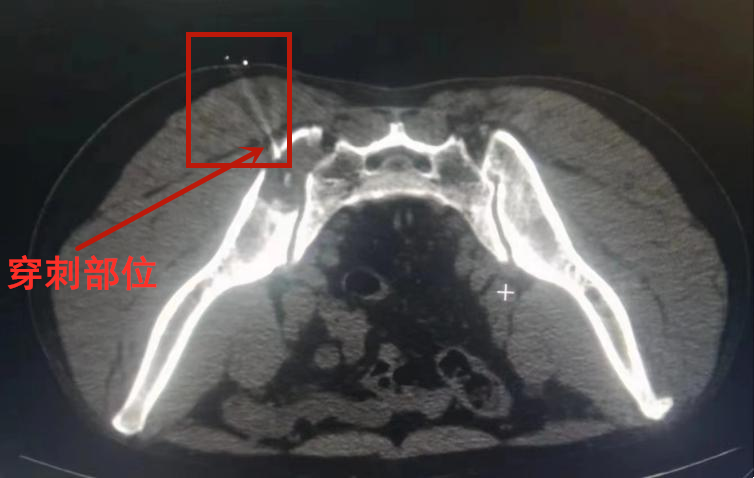

3月2日上午,各个团队准备就绪,在完成定位、局部麻醉等步骤后,放射介入科主任罗谞成与朱晖副教授在CT的引导下开始进行穿刺,穿刺针精准到达肿块原计划穿刺区域,在取得足量活检组织后按规范操作固定标本,送病理检查,前后过程仅用15分钟,相较于手术切开活检,大大缩短了手术时间,同时穿刺创伤小,穿刺成功率高。

穿刺针尖到达骨质边缘

穿刺针尖突破骨质结构,到达病理软组织的边缘